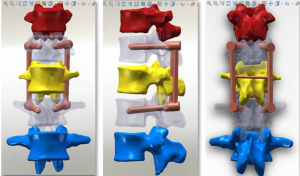

The three-dimensional entity model of T11–L3 and the screw-rod system were constructed using SolidWorks (Figures 7-9).

Meshing and supplemental establishment of the intervertebral disc and ligament: the three-dimensional entity models of T11–L3 and screw-rod system established in SolidWorks were imported into HyperMesh. Using the powerful mesh-making and dissection function of HyperMesh, a tetrahedral mesh was generated for the assembly, and 1-mm-thick cortical bone was constructed at the same time. The mesh sizes were 2 mm for T11–3 and 1 mm for the screw-rod system. Then, the structures of the endplate, annulus fibrosus, nucleus pulposus, anterior longitudinal ligament, posterior longitudinal ligament, intertransverse ligament, supraspinous ligament, interspinous ligament, ligamentum flavum, joint capsule ligament, and superior and inferior articular process cartilage were supplemented according to the anatomical site and shape to obtain a three-dimensional finite element model of T11–L3, which consisted of 191,386 elements and 55,741 nodes (the nodes and elements of T11–L3 Model Figure 10).

A three-dimensional finite element model of T11–L3 with the screw-rod system was obtained after the screw-rod system was added; it consisted of 310,970 elements and 73,469 nodes (the nodes and elements of T11–L3 Model with Pedicle Screw System Figure 11).